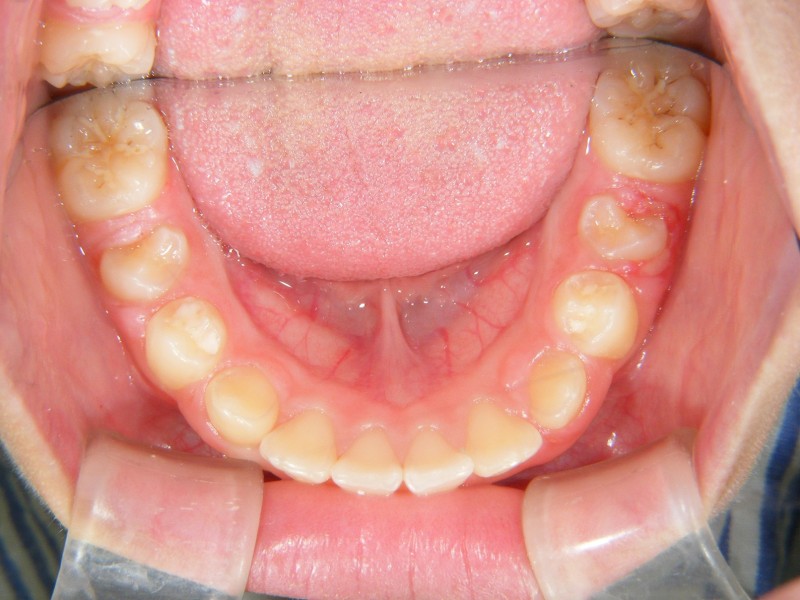

↑こちらは、奥歯も永久歯に生え変わった6年生の写真です。

上あごも狭かったので、下あごと同時に矯正治療しています。

このケース、前歯の凸凹が大きかったため、何もしないで永久歯への生え変わりを待っていたら、抜歯矯正になっていた可能性もあります。

早期に治療を開始したことにより、比較的簡単に、数個の装置で歯並びを改善することが出来ました。